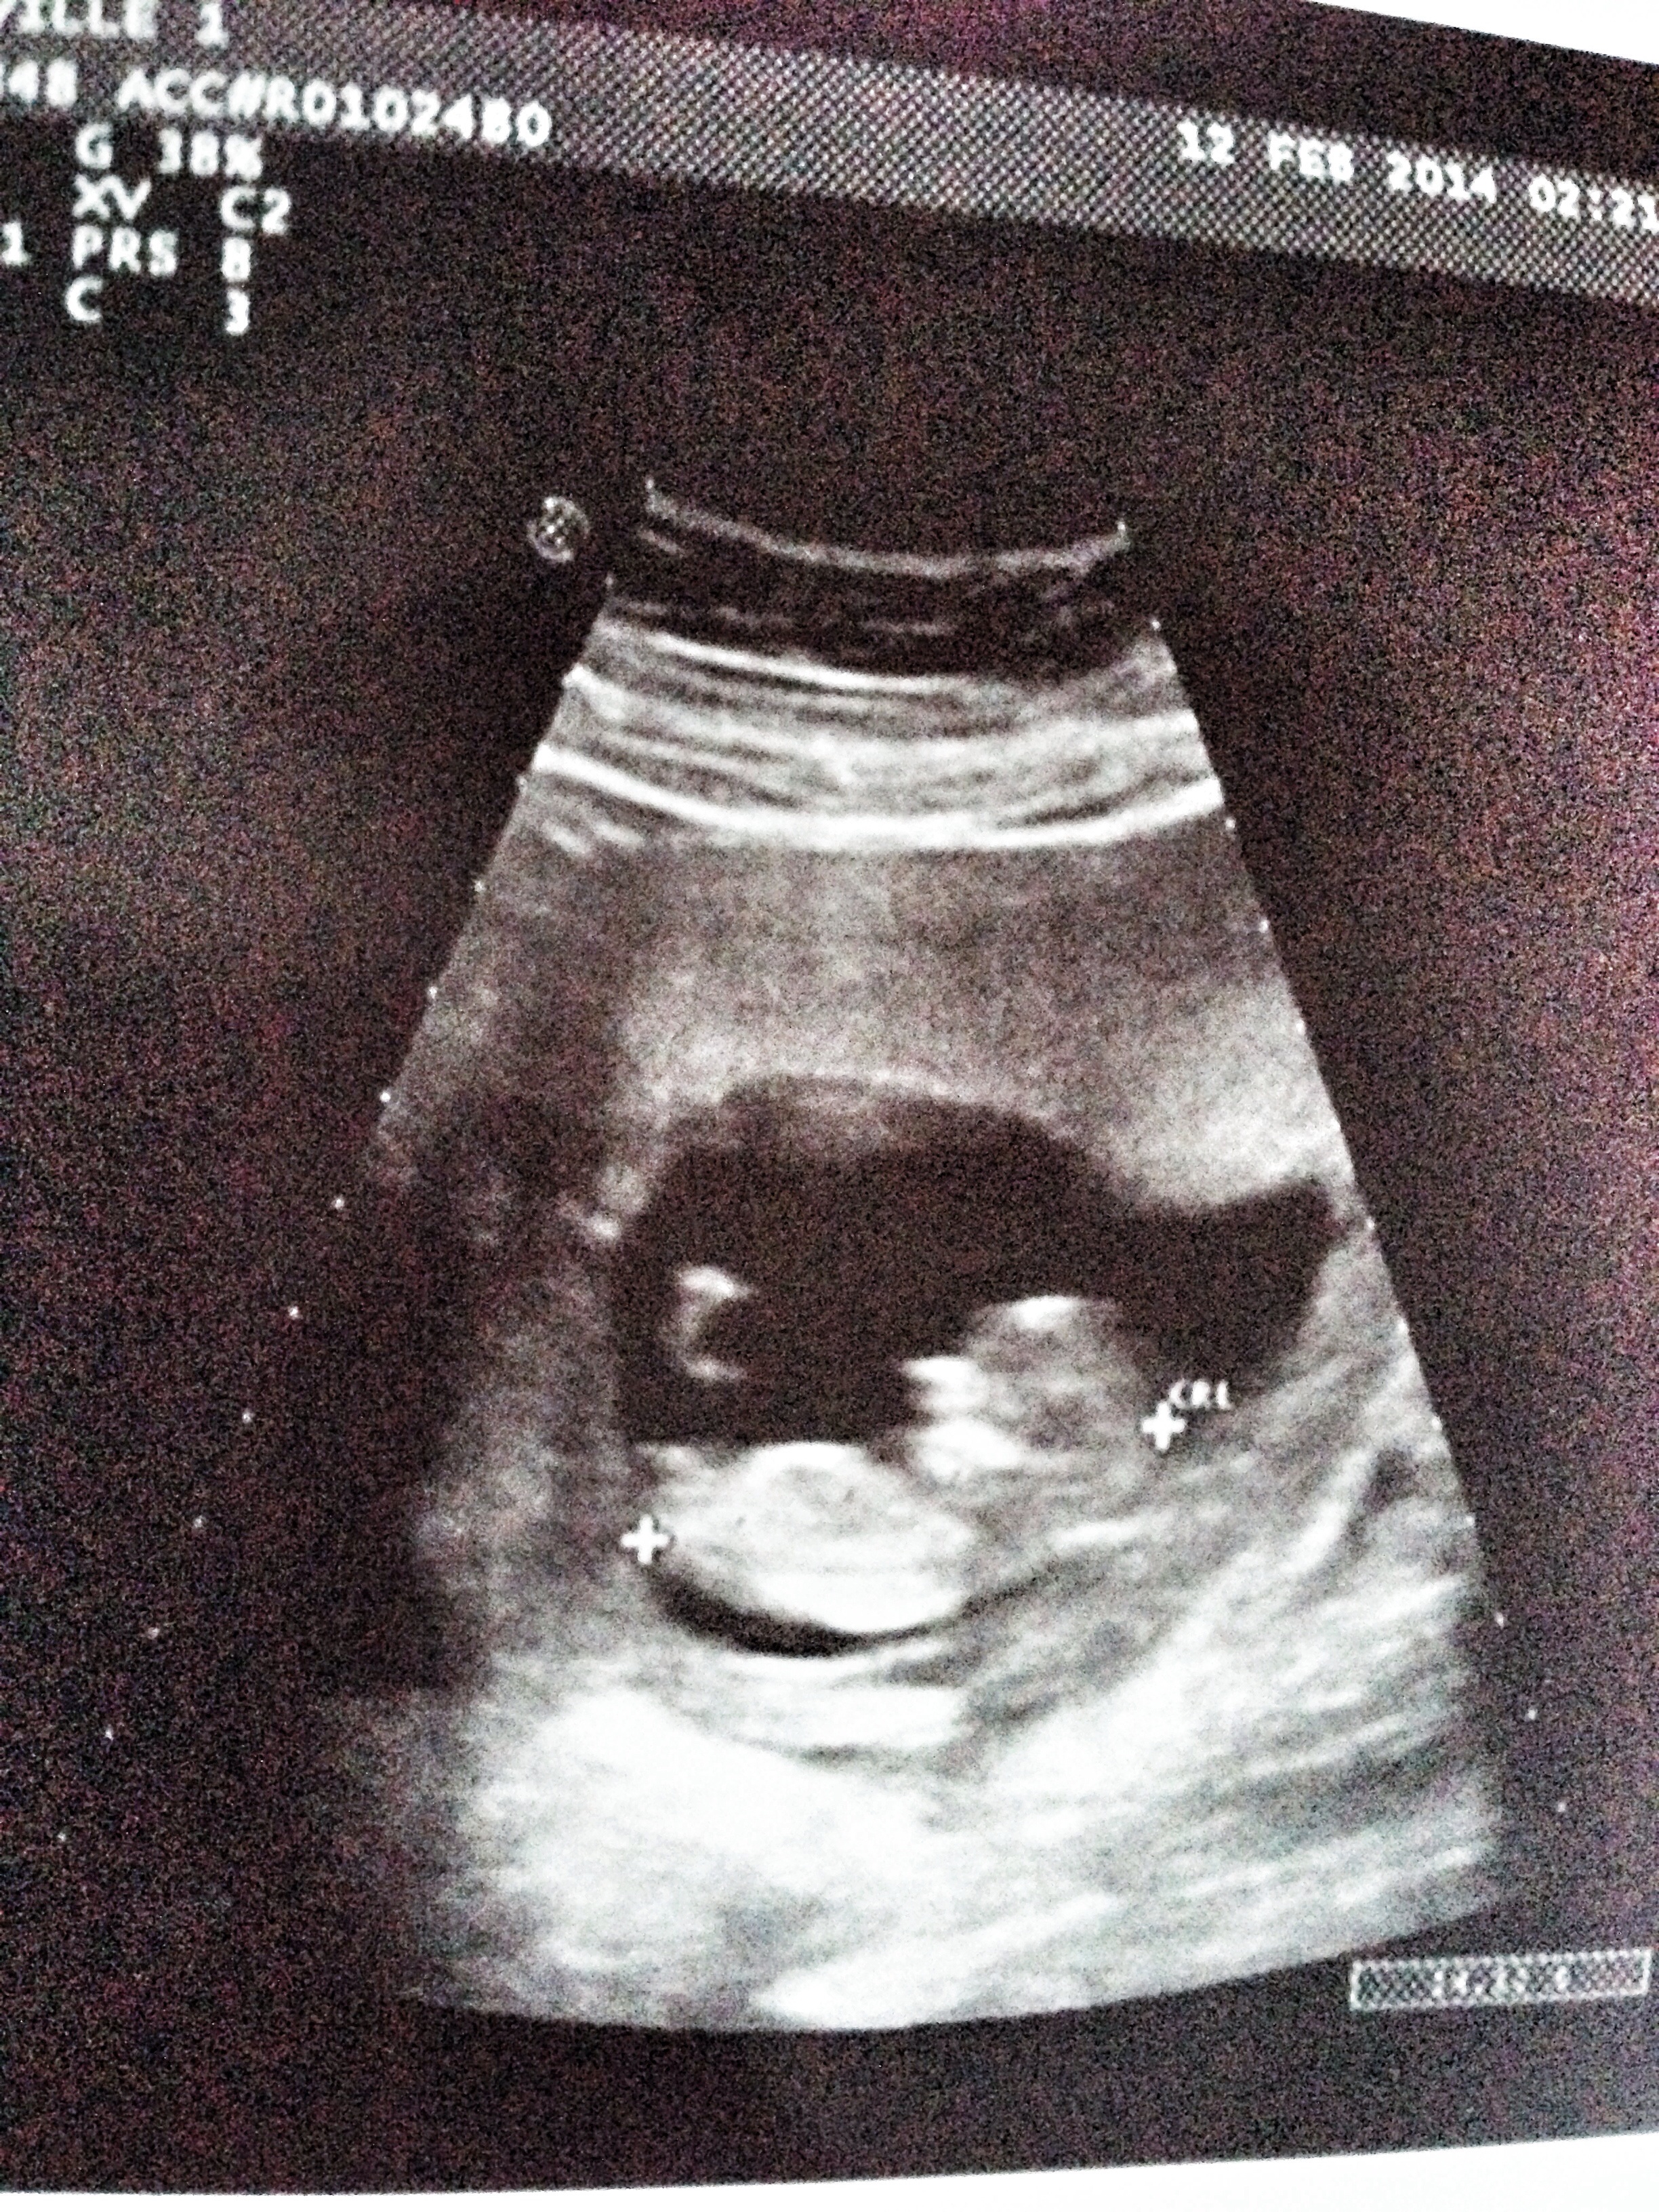

12 Week Ultrasound Gender Nub, Nub boy or girl? 12 weeks 3 days : Gender confirmed by harmony test!

12 Week Ultrasound Gender Nub, Nub boy or girl? 12 weeks 3 days : Gender confirmed by harmony test!. I thought i was 13 weeks according to my period but i had my first ultrasound and i was only actually 12 weeks. Check out my designer online children's. Ultrasound gender prediction » nub theory. Some people however believe in nub theory, which suggests you can determine the gender of your baby from that first ultrasound photo by. Check out our 12 week ultrasound, where we find out the gender of our baby!

Gender guesses. 12 weeks 4 days.

Predictions made by sonographers during routine obstetric ultrasound. Nub theory is now helping expecting mothers and parents to find out about the gender of their child. Anyone know about the nub theory? 12 +5 week ultrasound nub guess. If so, post it here for a gender prediction! Check out my designer online children's. Gender confirmed by harmony test! While every woman is different, you may have several ultrasounds over the course of the first 20 weeks of pregnancy.

My mom bawled her eyes out and you can hear. Find out the gender of your baby from 12 weeks with my current 97.2% overall accuracy!* using nub theory! I thought i was 13 weeks according to my period but i had my first ultrasound and i was only actually 12 weeks. Gender selection and gender prediction: A theory that really works, here's how to use your scan to predict your baby's the difficulties of early gender prediction | your pregnancy. What do the experts say about nub theory? Gender confirmed by harmony test! Predictions made by sonographers during routine obstetric ultrasound. Check out our 12 week ultrasound, where we find out the gender of our baby! This will help you a lot in preparing the nursery, decor, clothes. Did these theories work for you too? Knowing the gender in prior will help them prepare better for the new arrival in their family. Accuracy of sonographic fetal gender determination:

Do you think this is a boy or a girl? Find out the gender of your baby from 12 weeks with my current 97.2% overall accuracy!* using nub theory! Nub theory is now helping expecting mothers and parents to find out about the gender of their child. Natural gender selection, ivf/pgd experts | genderdreaming.com. While an ultrasound may predict gender as early as 12 weeks, dr.